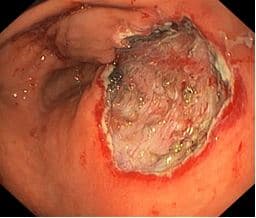

Область резекции слизистой оболочки в виде посткоагуляционного дефекта овальной формы, размером ~ 25 х 30мм, в дне дефекта отчетливо визуализируются соединительнотканные сплетения подслизистого слоя сетчатой структуры, пеньки тромбированных сосудов

На рисунке: Область резекции слизистой оболочки.